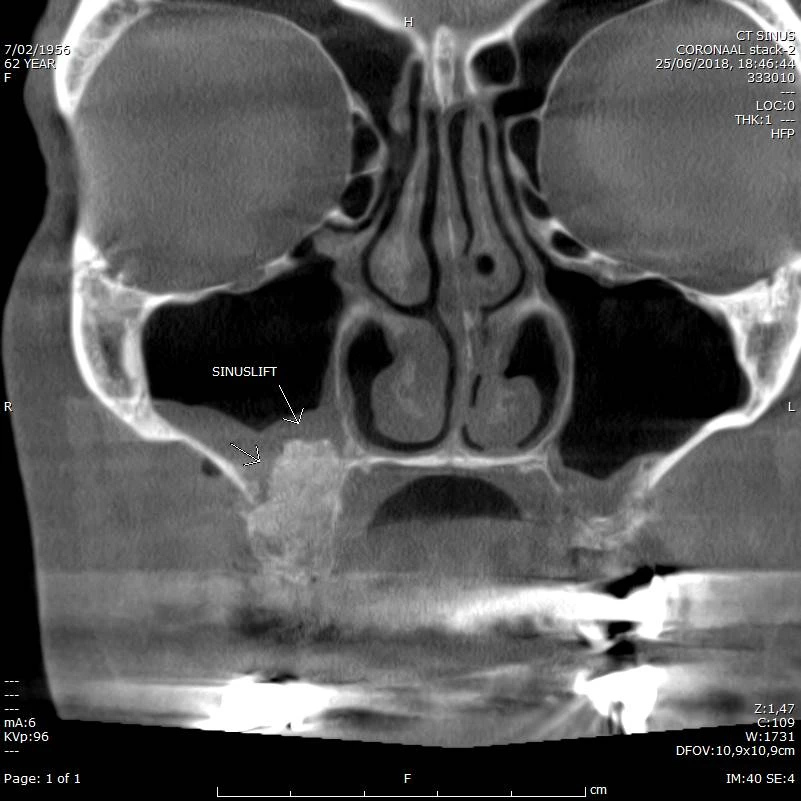

Follow up na Sinus Lift rechts (met veel metaal maxillair en mandibulair)

CBCT voorbeeld 6: sinuslift coronal

Coronale doorsnede: sinuslift rechts, veel metaal artefacten zichtbaar